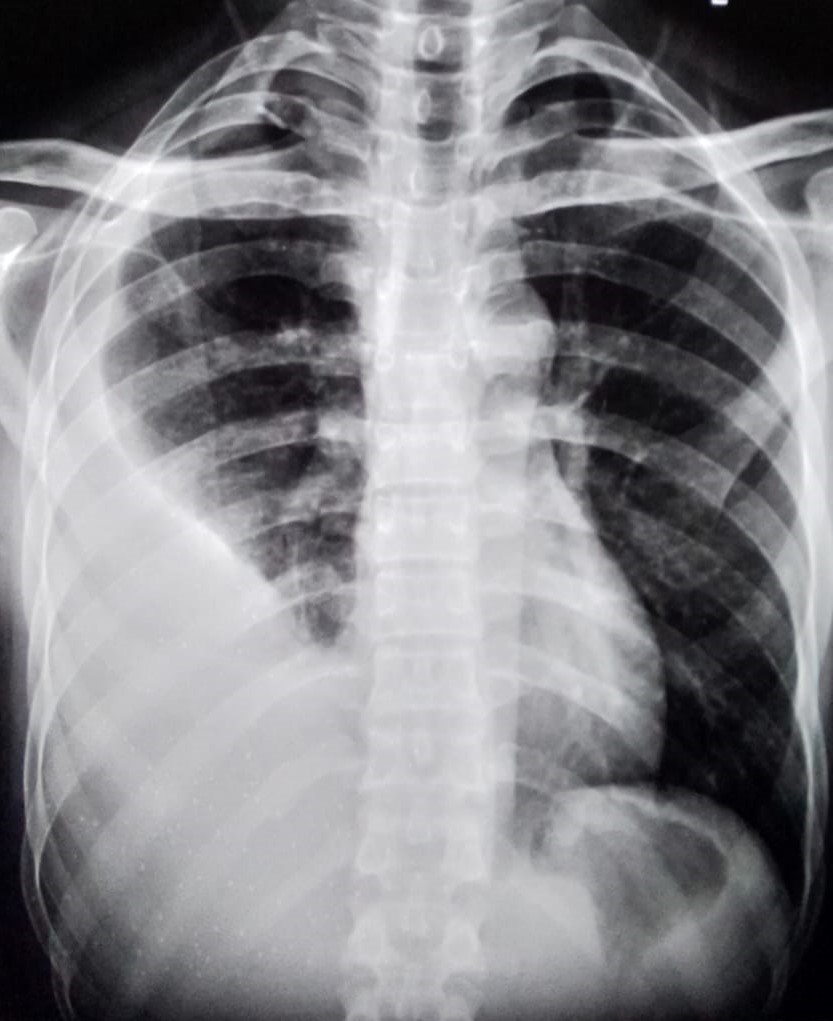

| 350 | IGGMC, Nagpur, Nagpur | P2 | 29-4122 | Pravin Thaware | Consent taken on Paper | 32 Yrs. |

Provisional Diag : Pre-Employment Medical fitness

Final Diag : CxR No Finding (Medical Fitness) |

Pure Normal Case (Cases with no complaint, NAD or medical fitness cases) | NODULAR OPACITIES SEEN IN BILATERAL HILAR REGION | No abnormality visible on x-ray |